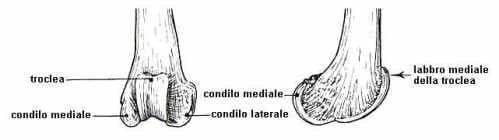

– la parte distale (o terminale) del femore: sulla faccia craniale (sul davanti, per intenderci) presenta una fossa, detta troclea, nella quale scorre la rotula nei movimenti di flessione ed estensione della gamba, mentre dietro a questa troviamo i condili, ovvero due grosse formazioni ovoidali che servono come appoggio sulla tibia;